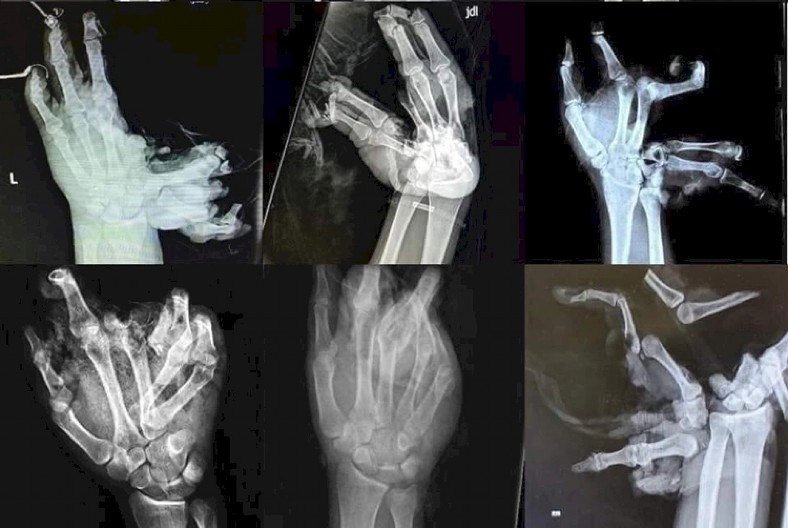

- „10 godina smo suprug i ja radili u Hitnoj pomoći. Sa nelagodom iščekujemo raspored dežurstava jer se ni jedan zdravstveni radnik ne raduje tom dežurstvu... A onda dođe 31. decembar. pesnica je u najlonu i peškiru, iz kojeg curi krv i padaju komadi kosti i kože u čekaonici zbog neveštog držanja uplakanih roditelja ili prijatelja koji su u strašnom šoku da je u stvarnosti 1000 puta strašnije + bolovi će biti brzi, ako i jedan prst može da se sačuva za sekundu euforije, ceo život će platiti invalidninom, zbogom društvo, zbogom , zbogom posla, najčešće je otac bio odgovoran za petardu u ruci deteta. Zato ako voliš sebe i druge, imaš divne planove, i srećan i bezbrižan život, onda ostavi petardu. onima koji su odlučili da budu nepovratno nesrećni“

Zato, dobro razmislite kada svom detetu dajete pirotehniku za doček... i uvek pamtite reči doktorke Zvezdane.